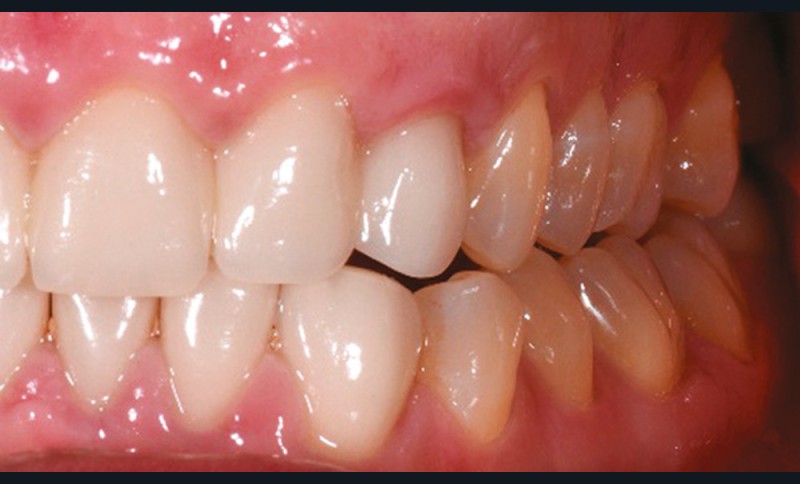

À l’examen endobuccal de première consultation (fig. 1), nous notons la présence d’un bridge maxillaire céramo-céramique sur infrastructure en zircone avec 12, 11, 21 et 22 couronnes moyens d’ancrage et 13 et 23 intermédiaires de bridge en extension. Les incisives et canines mandibulaires ont également été couronnées individuellement. Le patient nous informe que ces soins ont été réalisés pour répondre à sa demande esthétique. L’examen radiologique (fig. 2) révèle la présence de deux canines maxillaires incluses et nous montre qu’aucune dent n’a subi de traitement endodontique.